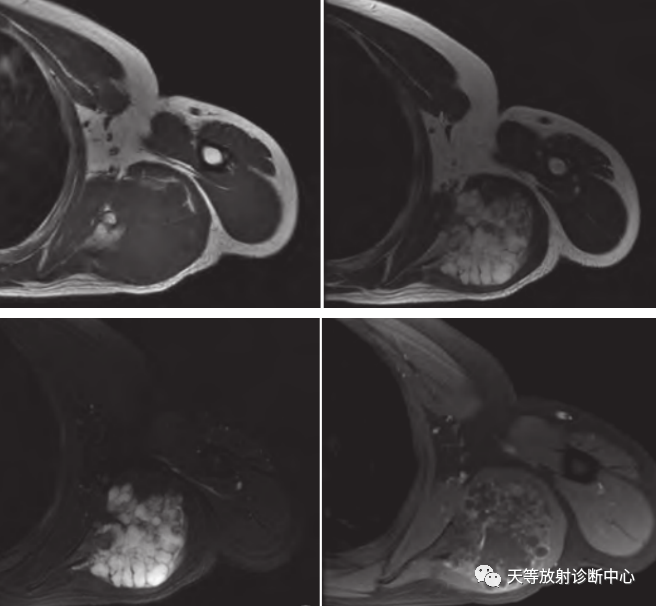

病例5:患者男,41岁,左侧肩胛骨软骨肉瘤。左侧肩胛骨骨质破坏伴软组织肿块,轴位T1WI示软组织肿块呈等信号,信号欠均;轴位T2WI及FS示软组织肿块呈明显高信号,其内见低信号间隔,肿块边界清晰;增强扫描小叶间隔明显强化,呈环状、弧状或不规则强化,环状强化主要位于病变外周区域,环状强化完整或不完整,不完整强化环缺口处多位于深面。

病例6:患者男,31岁,右侧肋骨软骨肉瘤。轴位T2WI软组织肿块呈明显高信号,小叶间隔呈低信号,中心钙化成分呈低信号,肿块边界清晰。冠位增强扫描软组织肿块呈环状及不规则强化,强化环多不完整,位于外周区域。

注:病例5、6来源:韩长年.软骨肉瘤的MRI强化特点[J].磁共振成像.2020.11(8):675-677.